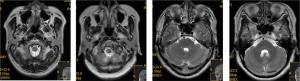

Cerebral MRI

Craniocerebral MRI examination

As shown in Figure 1, MRI monitoring revealed that patients in the CIRI group had multiple microbleeds outside the infarct in the brain and in the infarct area. The veins in the infarct area were significantly reduced or had disappeared on the contralateral side, and the veins had increased and thickened to varying degrees. T1W1 appeared as a moderately high signal in the low signal area, and T2W1 appeared as a low signal in the high signal area.

Cerebral vascular disease has the characteristics of high morbidity, mortality, and recurrence rate, and most frequently occurs in its ischemic form. Reperfusion of blood flow and restoration of blood oxygen supply are still the main principles of current clinical treatment (11). Although this kind of treatment can achieve occlusive cerebral vascular recanalization, it tends to further or irreversibly aggravate the pathological damage of ischemic tissue and worsen the clinical symptoms, which is known as CIRI. Current studies suggest that CIRI injury is closely related to excitatory amino acid toxicity, intracellular Ca2 overload, excessive generation of free radicals, and leukocyte-induced inflammatory response and cell apoptosis (12). However, the cytokines-induced by free radicals are also closely associated with CIRI. Free radical-induced adhesion molecules also play an important role in the development of reperfusion injury. Lipid, protein, and nucleic acid peroxidation are also caused by free radicals, which indirectly damage the membrane structure and causes protein degradation, destroying the nucleic acid backbone. This causes hyaluronic acid hydrolysis polymerization, cell disintegration, and mitochondrial degeneration, leading to irreversible changes in cells and eventual death. Free radicals and other messengers can stimulate ischemic cells to secrete inflammatory cytokines and chemokines, thus inducing the aggregation and infiltration of white blood cells in the cerebral ischemia site, which will aggravate the inflammatory response in the damaged site and form a vicious inflammatory response cycle (13). Patients are often not aware of the poor condition of their own disease, so the diagnosis of CIRI must rely on brain imaging diagnosis and differentiation. MRI is critical for the diagnosis of the vascular state of brain tissue after reperfusion of the brain in CVSD (14). In the present study, patients in the CIRI group had multiple microbleeds outside the infarct in the brain and in the infarct area. The veins in the infarct area were significantly reduced or disappeared from the contralateral side, and the veins increased and thickened to varying degrees. T1W1 appeared as a moderately high signal in the low signal area, and T2W1 appeared as a low signal in the high signal area, which suggests that MRI could detect early abnormal perfusion in the local brain tissue. MRI is widely used in brain diagnosis, and it is sensitive to the detection of cerebral apoplexy with microbleeds and arterial thrombosis. It can clearly display cerebral venules and sensitive detection of microbleeds. It has potential application value in the diagnosis and evaluation of CIRI (7).